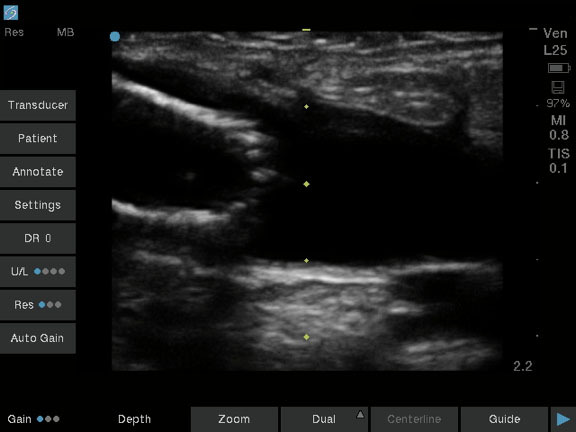

Dialysis Long View of Stent in Vessel Image